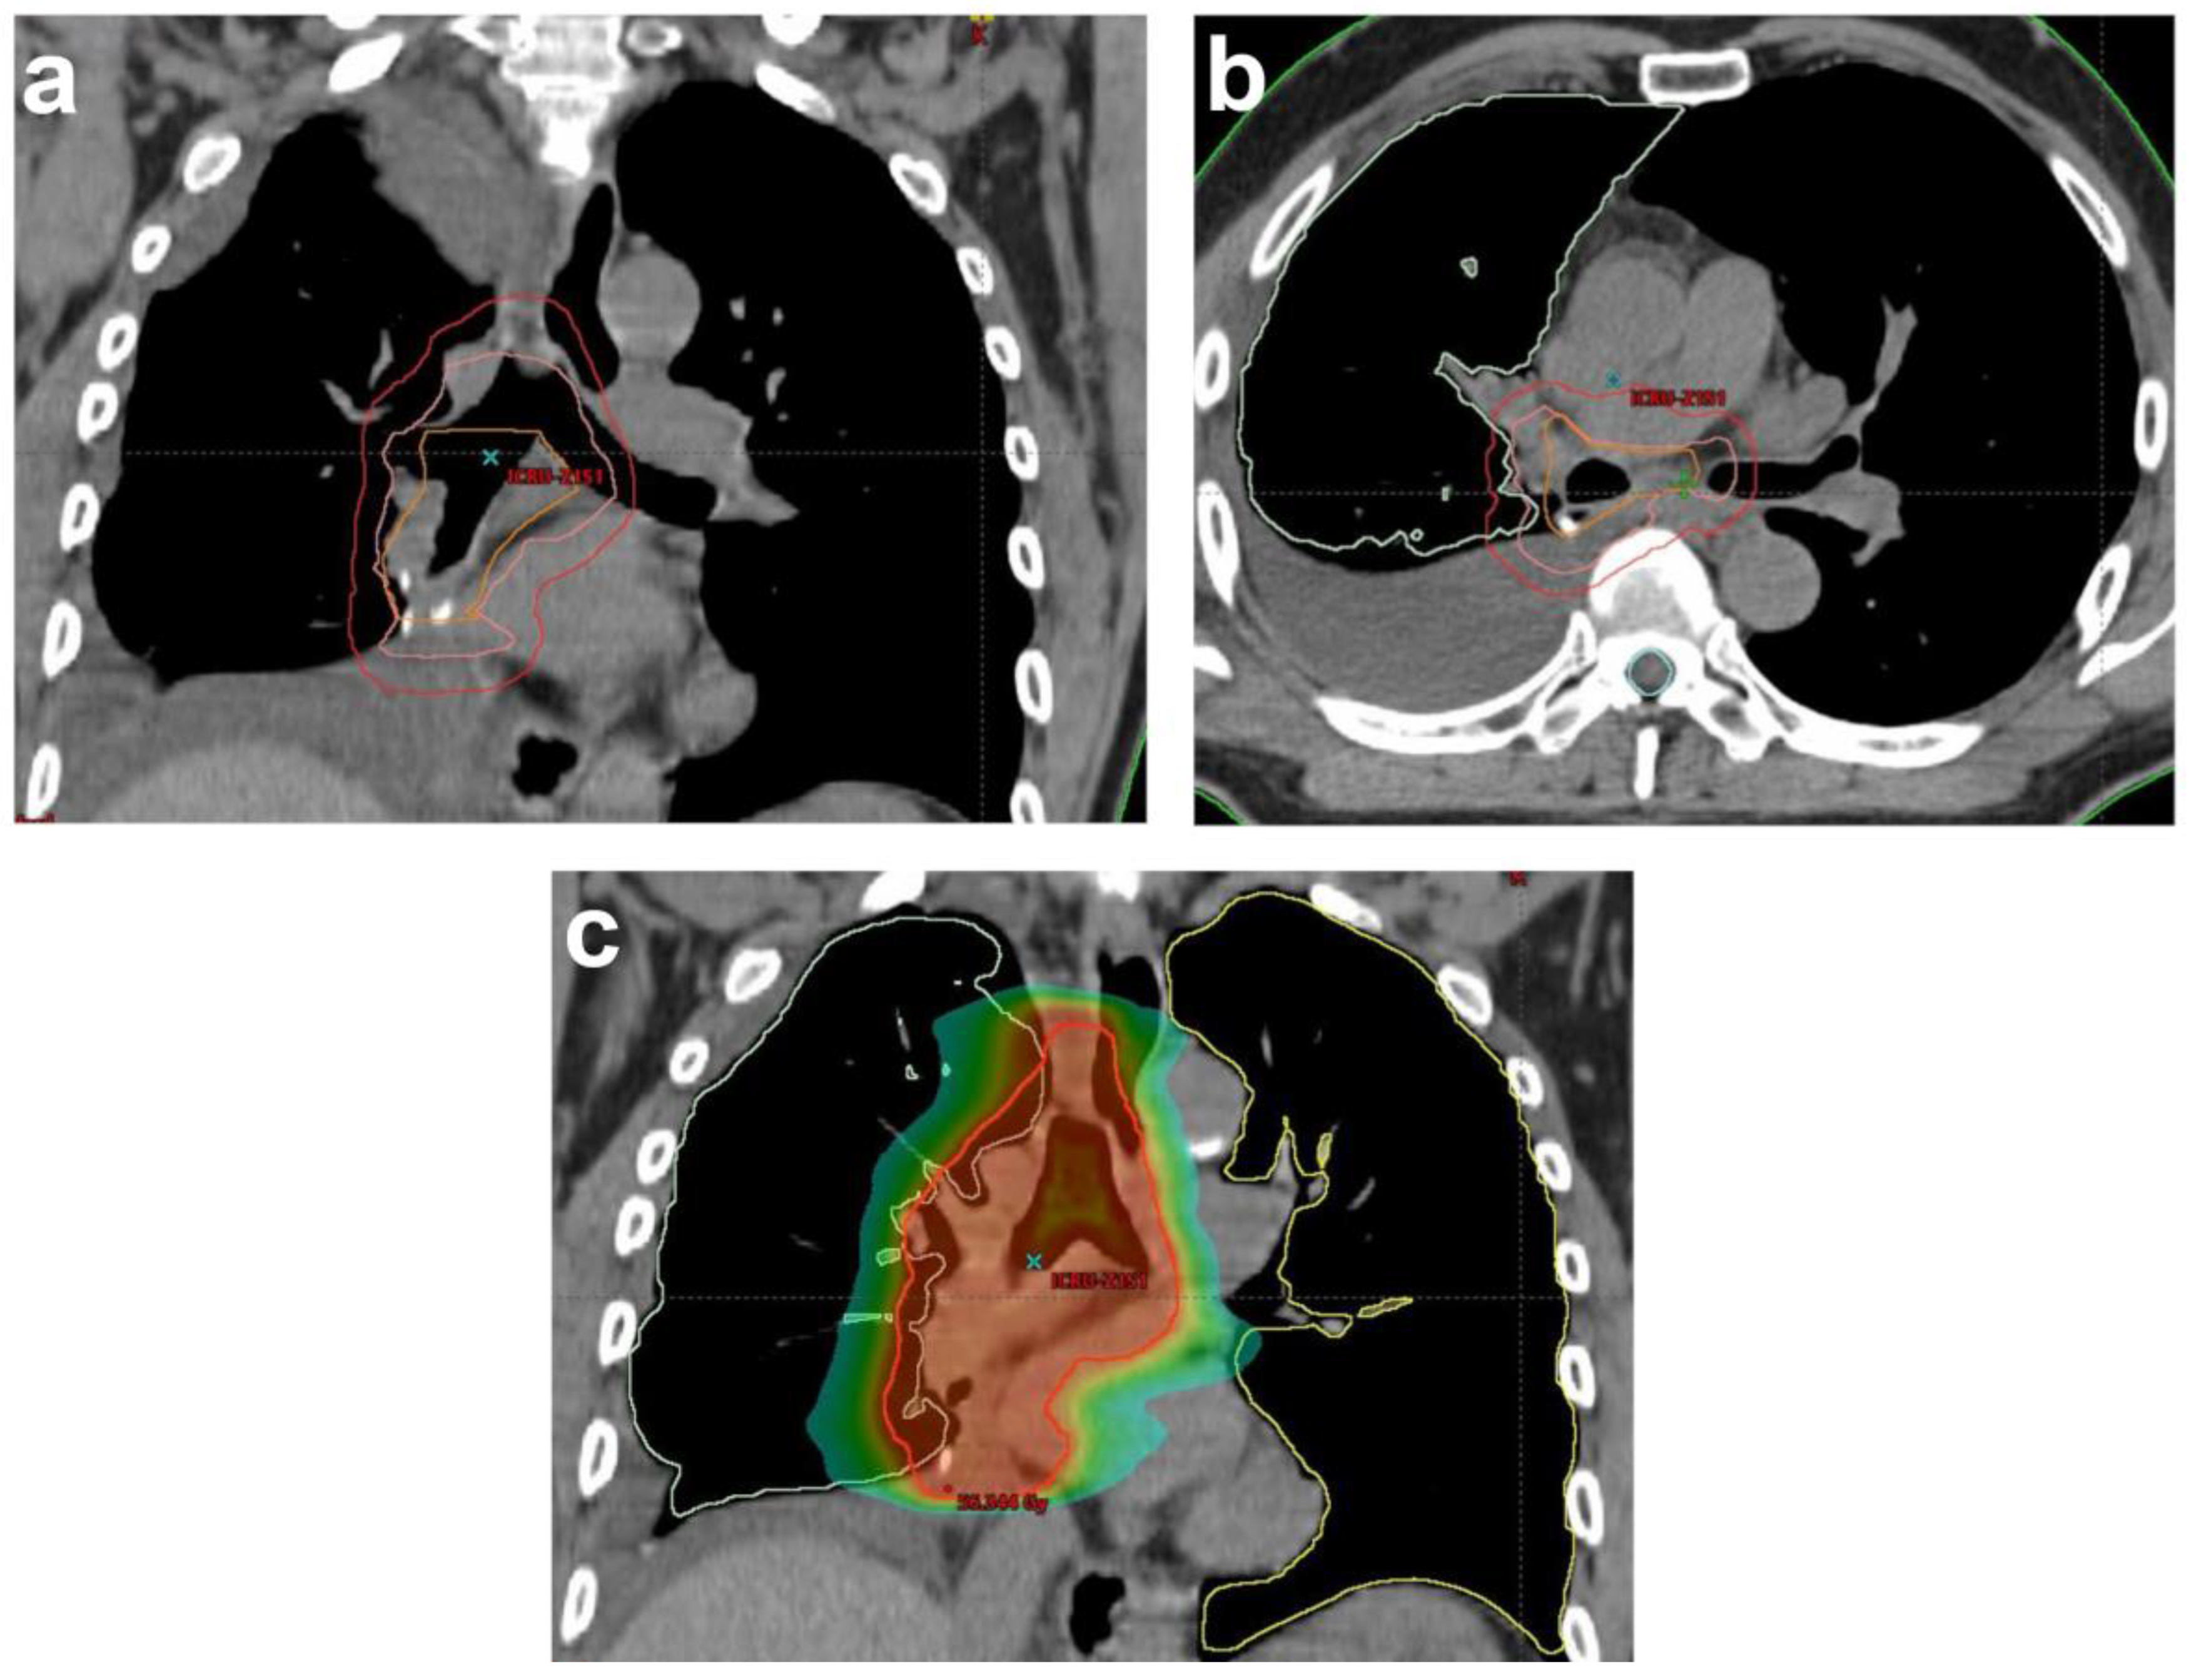

- Spoelstra, F.O.; Senan, S.; Le Péchoux, C.; Ishikura, S.; Casas, F.; Ball, D.; Price, A.; De Ruysscher, D.; de Koste, J.R.V.S.; Lung Adjuvant Radiotherapy Trial Investigators Group. Variations in target volume definition for postoperative radiotherapy in stage III Non–Small-Cell lung cancer: Analysis of an international contouring study. Int. J. Radiat. Oncol. Biol. Phys. 2010, 76, 1106–1113. [Google Scholar] [CrossRef]

- Billiet, C.; De Ruysscher, D.; Peeters, S.; Decaluwé, H.; Vansteenkiste, J.; Dooms, C.; Deroose, C.M.; De Leyn, P.; Hendrikx, M.; Bulens, P. Patterns of locoregional relapses in patients with contemporarily staged stage III-N2 NSCLC treated with induction chemotherapy and resection: Implications for postoperative radiotherapy target volumes. J. Thorac. Oncol. 2016, 11, 1538–1549. [Google Scholar] [CrossRef]

- Nestle, U.; De Ruysscher, D.; Ricardi, U.; Geets, X.; Belderbos, J.; Pöttgen, C.; Dziadiuszko, R.; Peeters, S.; Lievens, Y.; Hurkmans, C. ESTRO ACROP guidelines for target volume definition in the treatment of locally advanced non-small cell lung cancer. Radiother. Oncol. 2018, 127, 1–5. [Google Scholar] [CrossRef]